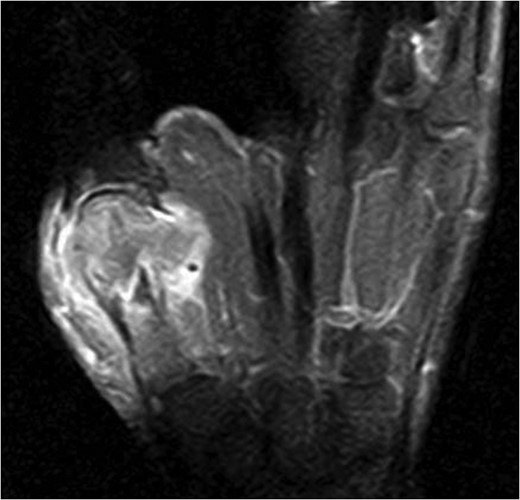

Fifteen months after surgery, the patient presented with redness, pain, and swelling of the right thumb. Radiography revealed right metacarpal bone destruction (Fig. 1). Technetium-99m HDP bone scintigraphy showed strong tracer accumulation in the right thumb (Fig. 2). T1-weighted magnetic resonance images revealed a mass lesion with a contrast effect (Fig. 3). Fluorine-18 fluorodeoxyglucose positron emission tomography also showed abnormal uptake in the right metacarpal bone, with no accumulation at other sites (Fig. 4). Lung and abdominal computed tomography scans showed no distant metastases or recurrence of the primary lesion, and serum tumor marker levels were normal.

T1-weighted magnetic resonance image revealing a mass lesion with a high contrast effect and soft tissue involvement.